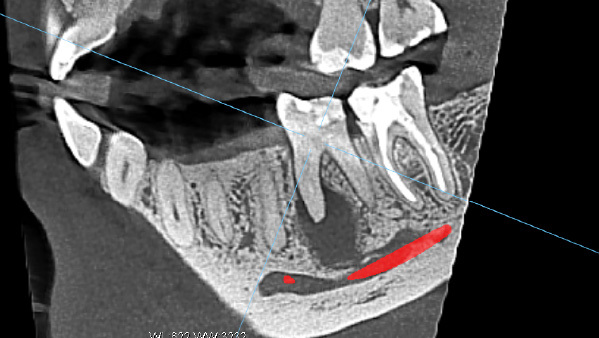

Как это часто бывает, пациенты не предъявляют жалобы при таких диагнозах. Так и в данном случае, пациента ничего не беспокоило. Кисту мы обнаружили на компьютерной томографии, которую сделали в профилактических целях.

Внешне: нарушение краевого прилегания пломбы, это когда она "отклеивается" от стенки зуба и видна как желтая полоска между пломбой и зубом, а также кариозное пятно на передней поверхности. Исходя из объема пломбировочного материала, врач сразу подозревает, что ранее зуб лечился в корневых каналах, а такие зубы требуют динамического контроля и покрытия коронками. Поэтому мы начали со снимка, на котором обнаружили большую кисту.